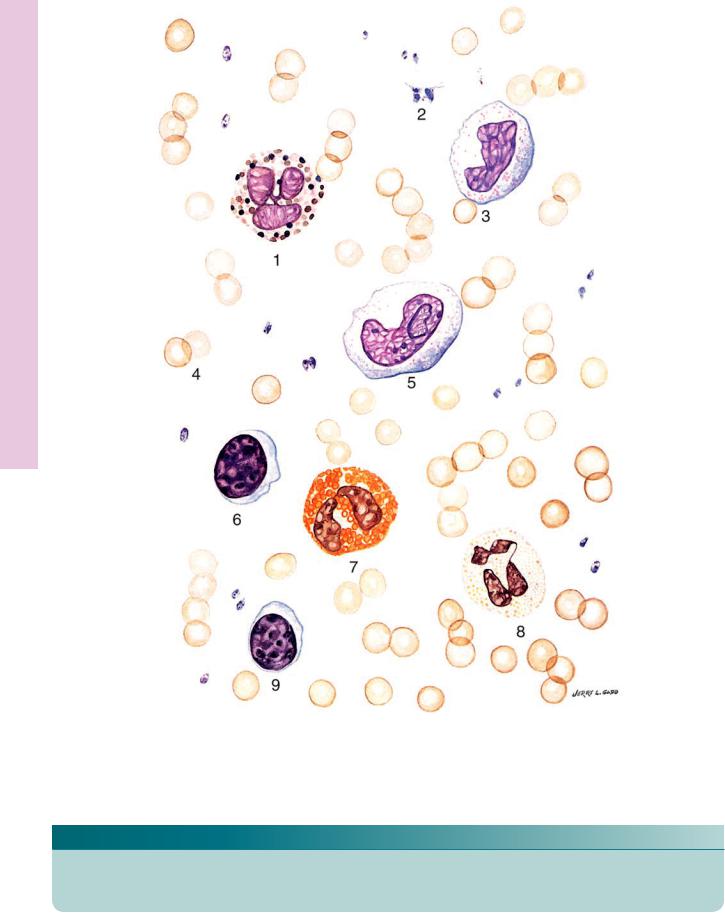

(Drawing) Blood Circulating • 2-5 PLATE

FIGURE 1

KEY

1. |

Basophil |

4. |

Erythrocytes |

7. |

Eosinophil |

2. |

Platelets |

5. |

Monocyte |

8. |

Neutrophil |

3. |

Monocyte |

6. |

Lymphocyte |

9. |

Lymphocyte |